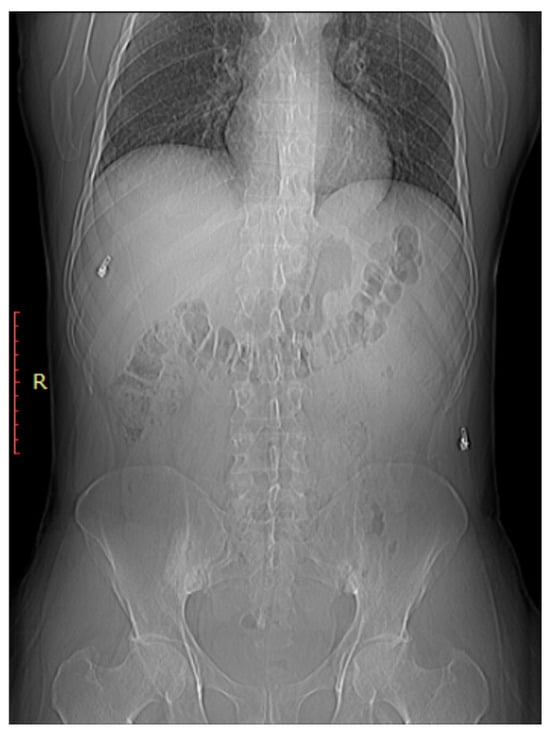

As shown in Figure 2, early sacroiliitis may show subtle erosions at the joint margins [44]. These erosions are typically irregular and may appear as small, well-defined areas of bone loss [44]. As the inflammation progresses, the joint may become more sclerotic, leading to increased bone density in the SI joint [45]. Progressive inflammation can lead to narrowing of the SIJ space, indicating joint damage and dysfunction As shown in Figure 3, early sacroiliitis may show subtle erosions at the joint margins [44]. These erosions are typically irregular and may appear as small, well-defined areas of bone loss [44]. As the inflammation progresses, the joint may become more sclerotic, leading to increased bone density in the SI joint [45]. Progressive inflammation can lead to narrowing of the SIJ space, indicating joint damage and dysfunction [1]. In addition, changes in the subchondral bone, including irregularities, sclerosis, and erosions, are common features of sacroiliitis [46].

Figure 3.

Bilateral sacroiliitis. X-ray for a 41-year-old male presenting with Rt sciatica showing irregularity and sclerosis of both sacroiliac joints is more evident on the right.